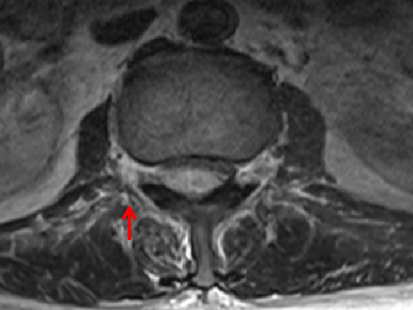

箭頭所指為鐘女士腰1至骶1節段膿腫

箭頭所指處可看出,受壓最嚴重部位脊髓已被擠壓成薄片狀